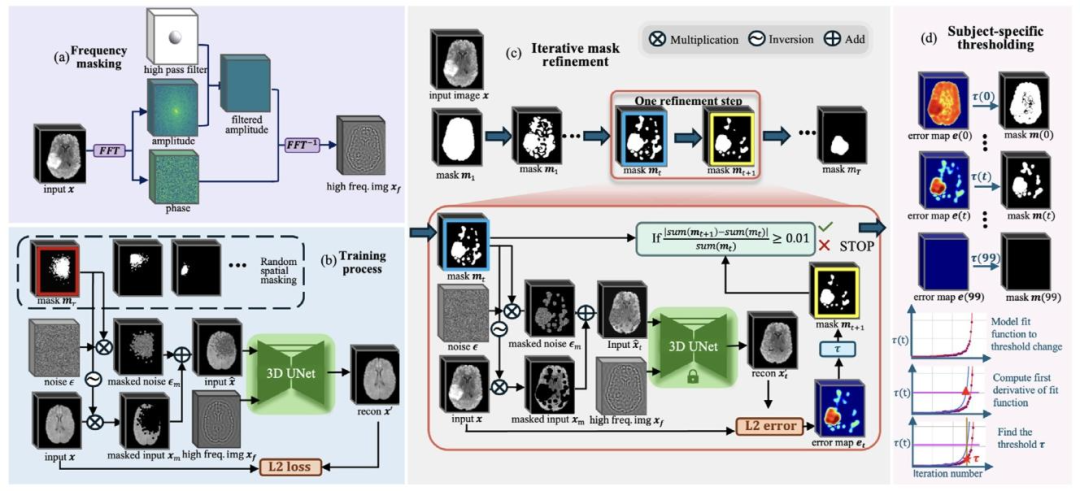

Our proposed method is a reconstruction-based unsupervised anomaly segmentation method. The training dataset, 𝐷**𝑡𝑟 = { 𝐱 𝑖 }𝑁𝑖*=1, consists of ‘normal’ in-distribution samples. The model aims to learn thetraining distribution following the ‘corrupt and reconstruct’ paradigmas previously introduced in Section 1, which learns to reconstructin-distribution samples after corruption. During testing, given testingdataset 𝐷**𝑡𝑒 = { 𝐱 𝑖 }𝑀𝑖*=1, the model aims to segment any patterns outsidethe training distribution (unseen during training) as anomalies. To mitigate the sensitivity-precision trade-off in reconstruction-based methods,we propose an iterative spatial mask refinement process, 𝐼 𝑡𝑒𝑟𝑀𝑎𝑠𝑘3𝐷,as shown in Fig. 2© Testing Process. To ensure large reconstructionerrors in abnormal regions for effective anomaly segmentation, spatialmasking is applied to completely mask anomalies before reconstruction.Additionally, to accurately reconstruct normal areas with minimal reconstruction error, we gradually shrink the mask towards the anomaly.This process progressively unmasks normal regions, providing the network with more information on case-specific ‘normal’ patterns to betterreconstruct normal areas under the mask.Specifically, as shown in Fig. 2© Iterative Mask Refinement, westart by masking the entire brain area. In each iteration, the network reconstructs the masked regions, and areas with small errors areidentified as normal and subsequently unmasked. With every iteration, more information is revealed, allowing the network to refine itsreconstruction.However, as the network is guided only by the unmasked regions,it must infer the missing structures in a generative manner. Incorrectly inferred structures will introduce reconstruction errors evenin normal areas, leading to false positives. To address this, we further propose incorporating high-frequency information (achieved vialow-frequency masking in the Fourier space) to guide the structuralreconstruction of masked regions, as shown in Fig. 2(a). In each iteration, the threshold for identifying normal regions is decided by theSubject-specific thresholding* strategy, as shown in Fig. 2(d). As the maskis progressively shrunk by a fixed proportion, the threshold is selectedbased on the characteristic change in threshold values throughout themask-shrinking process.Finally, the training process is depicted in Fig. 2(b). To train thereconstruction model, we apply randomly generated Gaussian masks asspatial masks to the input image and combine them with input of highfrequency components (generated as shown in Fig. 2(a)). The model istrained to reconstruct the masked regions using this combined input. Inthe following sections, we introduce Iterative Spatial Mask Refinement(Fig. 2©) in Section 3.2, frequency masking (Fig. 2(a)) in Section 3.3,subject-specific thresholding strategy (Fig. 2(d)) in Section 3.4, and thetraining process (Fig. 2(b)) in Section 3.5.

3.1 方法概述 本文提出的方法是一种基于重建的无监督异常分割方法。训练数据集(D{tr}={x_i}{i=1}N)由“正常”的分布内样本构成。模型旨在遵循第1节中介绍的“损坏-重建”范式来学习训练数据分布,即学习对损坏后的分布内样本进行重建。 测试阶段,给定测试数据集(D{te}={x_i}{i=1}M),模型旨在将训练分布之外(训练过程中未见过)的所有模式分割为异常。为缓解基于重建的方法中存在的“灵敏度-精度权衡”问题,我们提出了一种迭代式空间掩码优化流程——IterMask3D,如图2(c)“测试流程”所示。 为确保异常区域产生较大重建误差,从而实现有效的异常分割,在重建前会采用空间掩码对异常区域进行完全掩盖。此外,为精准重建正常区域并将其重建误差降至最低,我们会逐步将掩码向异常区域收敛。这一过程会逐步解除对正常区域的掩码,为网络提供更多特定病例的“正常”模式信息,从而更好地重建掩码下的正常区域。 具体而言,如图2(c)“迭代式掩码优化”所示,我们首先对全脑区域进行掩码处理。在每次迭代中,网络会对掩码区域进行重建,将误差较小的区域判定为正常区域,并随后解除对这些区域的掩码。每迭代一次,就会有更多信息被揭示,网络得以优化其重建效果。 然而,由于网络仅受未掩码区域的引导,它必须以生成式方式推断缺失的结构。即便在正常区域,推断错误的结构也会引入重建误差,进而导致假阳性。为解决这一问题,我们进一步提出融入高频信息(通过在傅里叶空间中进行低频掩码实现),以指导掩码区域的结构重建,如图2(a)所示。 在每次迭代中,判定正常区域的阈值由“特定于被试的阈值设定”策略确定,如图2(d)所示。当掩码按固定比例逐步缩小时,会根据整个掩码缩小过程中阈值的特征变化来选择最终阈值。 最后,训练流程如图2(b)所示。为训练重建模型,我们将随机生成的高斯掩码作为空间掩码应用于输入图像,并将其与高频成分输入(生成方式如图2(a)所示)相结合。模型通过这种组合输入进行训练,以实现对掩码区域的重建。 在后续章节中,3.2节将介绍迭代式空间掩码优化(图2(c)),3.3节介绍频率掩码(图2(a)),3.4节介绍特定于被试的阈值设定策略(图2(d)),3.5节介绍训练流程(图2(b))。

Fig. 2. Overview of the proposed approach. (a) Frequency-based masking: Extract structural information 𝑥𝑓 with a high-pass filter to isolate the high-frequencycomponents of the image. (b) Training process: Input image 𝑥 is masked using random spatial masking, and the model learns to reconstruct the masked area with𝑥𝑓* generated in (a) as an auxiliary input. © Iterative mask refinement: Iterative refinement of the spatial mask, where the mask 𝑚𝑡 at iteration 𝑡 gradually shrinkstowards the anomalous region. This refinement is guided by the spatially unmasked portions of the image 𝑥𝑚 and 𝑥𝑓 from (a). (d) Subject-Specific Thresholding:This component illustrates how the threshold 𝜏 is determined for iterative mask refinement on a per-sample basis. The mask is progressively shrunk by 1% ofthe brain volume at each time step 𝑡 until it fully disappears. We model 𝜏(𝑡) using a fitted function, and compute its derivative to identify the point where thethreshold begins to change abruptly. This point is selected as the sample-specific threshold 𝜏 for the current sample.

图2 所提方法概述 (a)基于频率的掩码:通过高通滤波器提取结构信息(x_f),以分离图像的高频成分。 (b)训练流程:采用随机空间掩码对输入图像(x)进行掩码处理,模型以(a)中生成的(x_f)作为辅助输入,学习对掩码区域进行重建。 (c)迭代式掩码优化:对空间掩码进行迭代优化,其中第(t)次迭代时的掩码(m_t)逐步向异常区域收敛。该优化过程由图像的未掩码部分(x_m)及(a)中生成的(x_f)共同引导。 (d)特定于被试的阈值设定:该模块展示了如何为每个样本的迭代式掩码优化确定阈值(\tau)。在每个时间步(t),掩码按脑体积的1%逐步缩小,直至完全消失。我们通过拟合函数对(\tau(t))建模,并计算其导数以确定阈值开始急剧变化的临界点,该临界点被选为当前样本的特定阈值(\tau)。